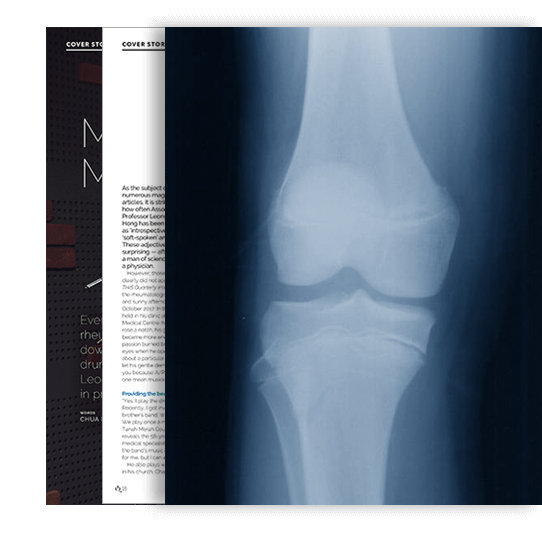

OSTEOPOROSIS COMES FROM THE GREEK, MEANING “porous bones”. It is a disease in the bones that leads to an increased risk of fracture. Bones become brittle and break easily, even after very little trauma, for example falling at home. This is different from the traumatic fractures that occur after road accidents. The bones that most commonly break are around the wrist, the spine and the hip.

When suffering from osteoporosis the bone mineral density is reduced, the bone microarchitecture deteriorates, and the amount and variety of proteins in the bone is altered. There might not be any symptoms in the early stages of this condition until a fracture occurs. People with osteoporosis may suffer from spinal compression fractures resulting in a loss of height with a stooped back, also known as dowager’s hump.